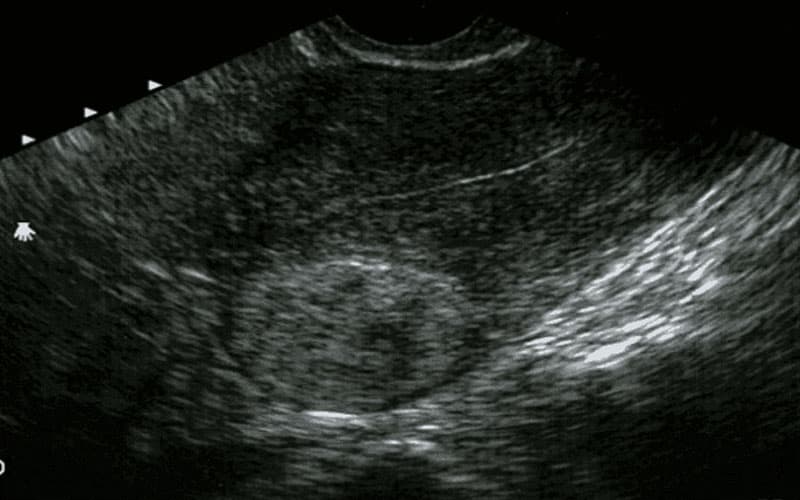

Theo dõi định kỳ là yếu tố bắt buộc đối với người đã được chẩn đoán u cơ trơn tử cung. Siêu âm mỗi 3 – 6 tháng giúp đánh giá kích thước và tốc độ phát triển của khối u. Riêng u cơ trơn cổ tử cung cần được theo dõi kỹ hơn bằng siêu âm đầu dò và soi cổ tử cung để phát hiện sớm tình trạng chèn ép đường sinh dục hoặc tiết niệu. Trong các trường hợp khối u ở cổ tử cung gây đau, cản trở kinh nguyệt hoặc ảnh hưởng sinh hoạt tình dục, phẫu thuật bóc nhân xơ thường được chỉ định sớm.